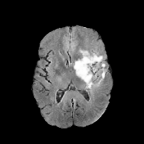

Brats MRI T1 Scans, FLAIR, Tumors. Lastly, we used a dataset of brain MRI scans [28] with two modalities: T1 (naive) and FLAIR (T2 Fluid Attenuated Inversion Recovery) [15]. We adapt the protocol that Cohen et al. [9] used for the Brats2013 datasets [27] to the more recent Brats2018 [3] dataset by varying the percentage of scans with tumors in the target domain. We selected transverse slices from the to range in the caudocranial direction [1] for both T1 and FLAIR scans. Each scan was classified as tumorous if more than of its pixels were labeled as such, and as healthy if it contained no tumor pixels. The training set contains images from each modality, with all source images (T1) being healthy and the target domain (FLAIR) comprising tumorous scans. The test set contains paired scans of healthy brains.

Qualitative Results. Figure 3 showcases StegoGAN’s qualitative performance against other image translation algorithms. Notably, StegoGAN effectively avoids generating unmatchable classes such as texts, highways, and tumors, while producing high-quality image translations.

Quantitative Results. On the PlanIGN dataset (Table 1) and the Brats MRI dataset (Table 2), StegoGAN outperforms others in fidelity, achieving the lowest RMSE by a margin of on PlanIGN and by for Brats MRI. Furthermore, it significantly enhances pixel accuracy, with improvements of in Acc() and in Acc() on PlanIGN. In the MRI dataset, StegoGAN dramatically reduces false positive rates—–over 20 lower than CycleGAN and 10 less than the next best model SRUNIT (for pFPR).

We adapt the protocol of Cohen et al. [9] from the Brats2013 datasets [27] to the more recent, larger, and more diverse Brats2018 dataset [2]. We consider two MRI modalities: native (T1) and Fluid Attenuated Inversion Recovery (FLAIR). We selected transverse slices from the to range in the caudocranial direction [1] for both modalities of scans.

We label each scan as tumorous if more than of its pixels are labelled as such, and as healthy if it contains no tumor pixels. We only use high-grade gliomas (HGG) instead of low-grade gliomas (LGG) as the are more easily observable [24]. In total, we obtain 5035 pathological pairs and 1135 healthy pairs. The train set is composed of a source domain of T1 images of healthy brains, while the target domain set is composed of FLAIR scans of which (60%) are tumorous and healthy. The test set is composed of aligned scans of healthy brains in both modalities.